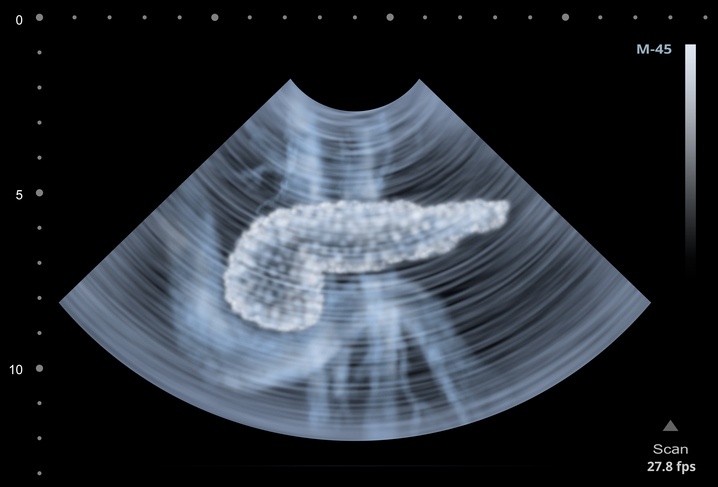

Gastroenterología / Pancreatitis Autoinmune

Diagnóstico de la pancreatitis autoinmune